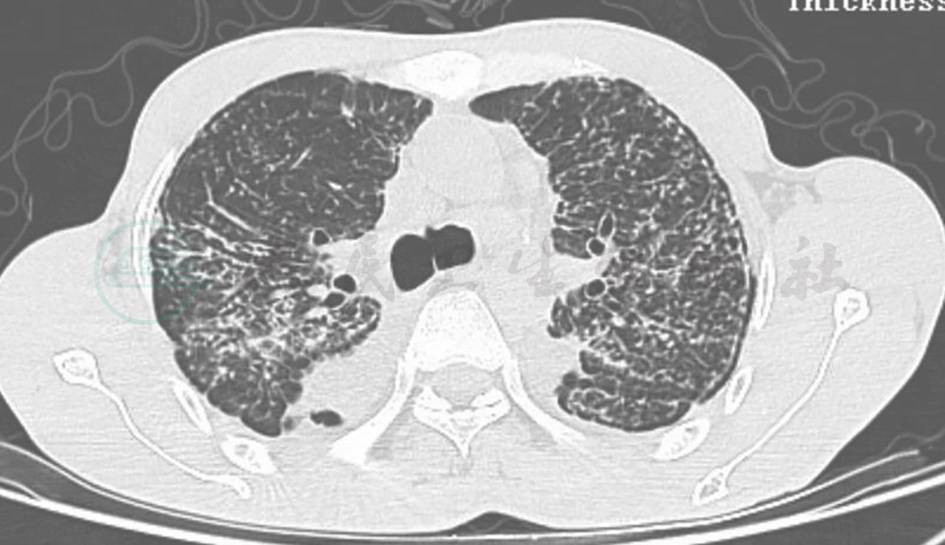

图3 弥漫性泛细支气管炎胸部CT表现

男性患者,58岁,因间断发热伴腹泻2个月余入院,既往有胸腺瘤手术史。胸部CT提示弥漫性小叶中心型结节影以及磨玻璃影。肺功能检测提示轻度混合性通气功能障碍